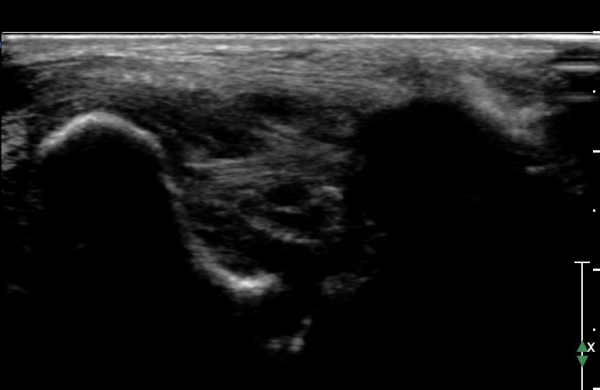

Àü°ÅºñÀδë ÇϺΠÁ¾´Ü¸é°Ë»ç¿¡¼­ Àü°ÅºñÀδëÀÇ Àú¿¡ÄÚ À§Ãø°ú Á·±Ùµ¿ÀÇ ¼ö¾×Àú·ù°¡

°üÂûµÈ´Ù(»çÁø 2, 3, 4).